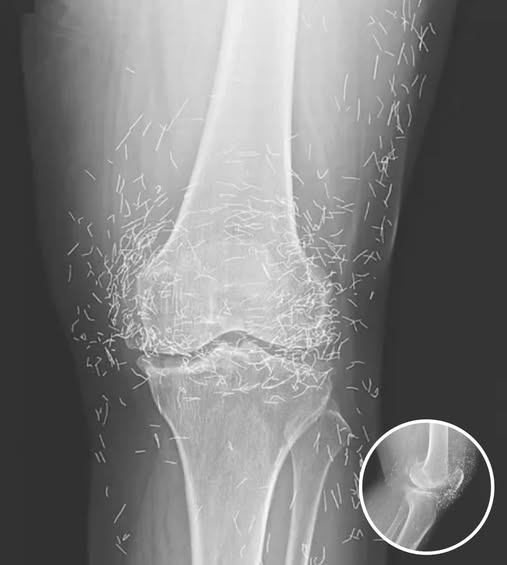

In this case, the needles were intentionally left in her body as part of a long-term treatment strategy. Some practitioners believe that leaving gold needles or threads in place can provide ongoing stimulation to the affected area. However, medical professionals warn that this approach carries significant risks.

Dr. Ali Guermazi, a radiology expert from Boston University not involved in the case, explained that the human body can react negatively to foreign objects. Inflammatory responses, tissue damage, and infections are potential complications. Additionally, the embedded needles can interfere with medical imaging, making diagnosis more difficult.

One of the most serious risks comes with MRI scans. The powerful magnetic forces used in MRIs can cause metal objects to move within the body, possibly leading to punctured blood vessels or other life-threatening injuries. This makes metal implants a critical concern for patients who may need future imaging.